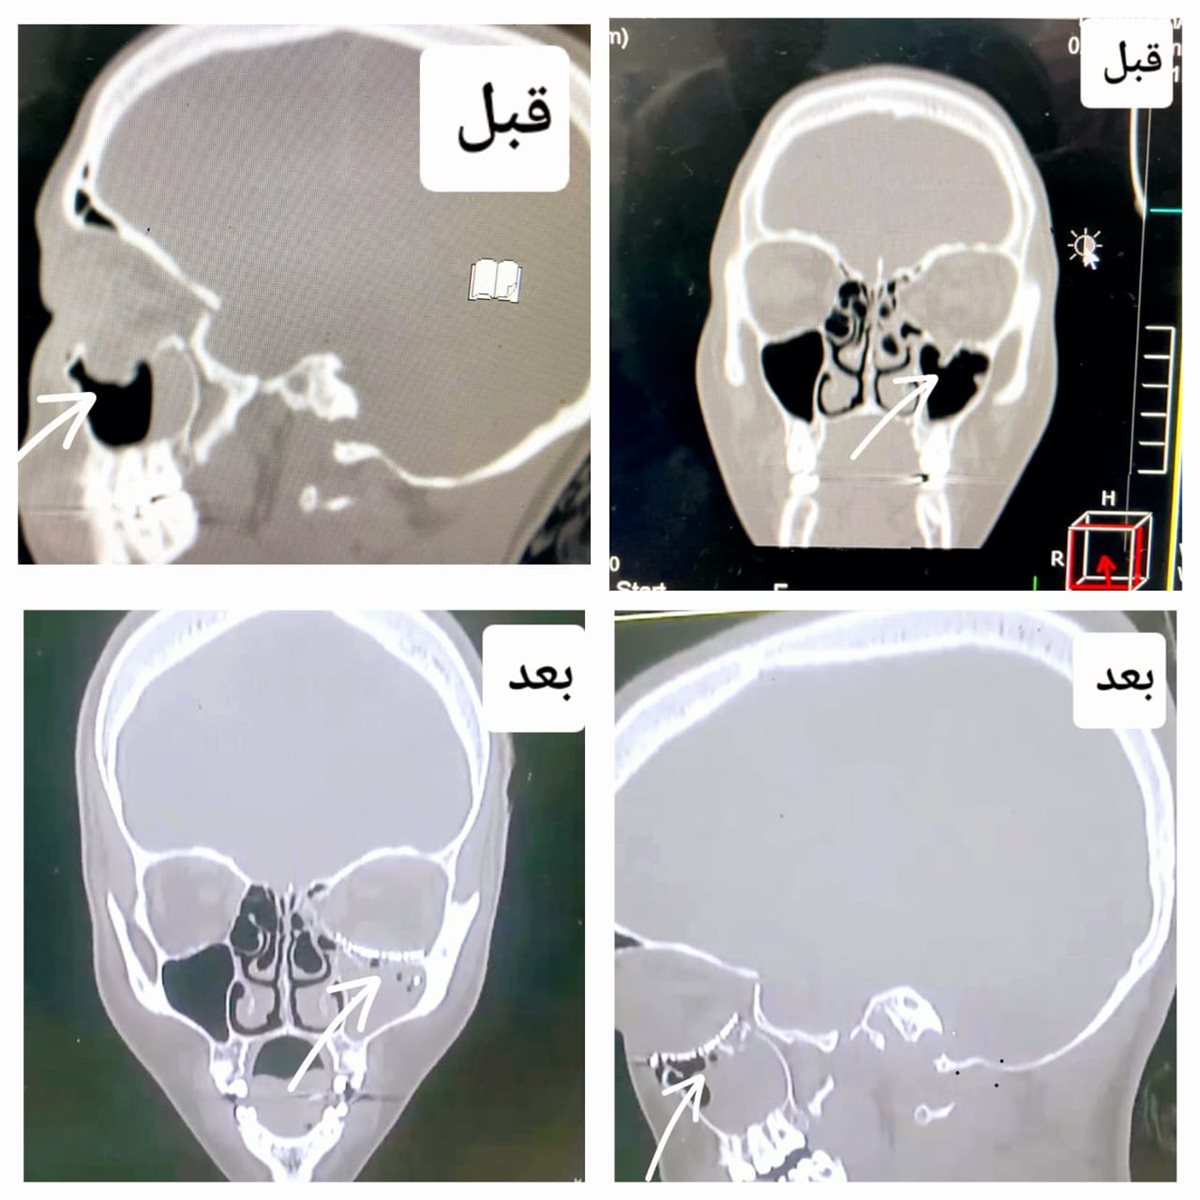

أكد الدكتور تامر مدكور وكيل وزارة الصحة بالدقهلية أن فريق طبي في مستشفى أجا قد نجح في إجراء أول عملية لإعادة بناء قاع العين حيث تعتبر من العمليات الكبرى والمعقدة في جراحة الوجه والفكين.

وأضاف مدكور أن مستشفى أجا كانت قد استقبلت مريضة تعاني من كسر بقاع العين أدي إلى حدوث خلل بعضلات العين وازدواجية بالرؤية نتيجة الكسر وتم عمل فحص للعين والتأكد من سلامتها وومن ثم تجهيز المريضة للعمليات.

بدوره أكد الدكتور أحمد البيلى وكيل المديرية للطب بالعلاجى أن العملية كأول عملية بعد افتتاح قسم جراحة الوجه والفكين في المستشفى مؤخرًا والذي يقوم بتشخيص وعلاج وجراحة كسور الوجه والفكين والجمجمة والأورام الحميدة والانتانات المرضية في الوجه والفكين وعلاج أمراض التشوهات الخلقية في الوجه والفكين.